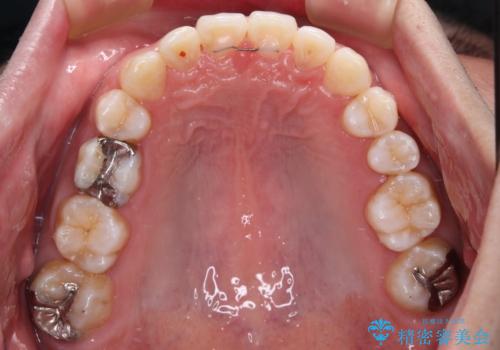

右上と左下は永久歯が欠如しており、大きさの大きく異なる乳歯が残存していたため、奥歯の咬み合わせを構築するために苦労しました。

元々隙間の空いていた上顎の正中は、後戻りのリスクが高いため、下顎前歯同様ワイヤー固定を行いました。